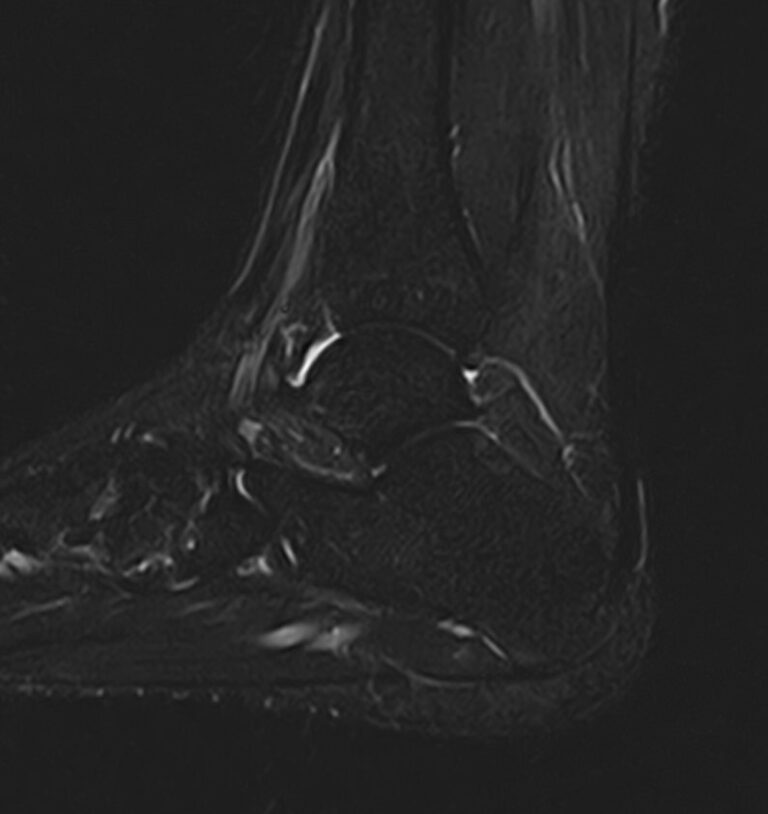

Наиболее точным и достоверным методом диагностики заболеваний голеностопного сустава является магнитно-резонансная томография. МРТ дает максимально полную информацию о состоянии всех анатомических структур сустава, включая костную ткань, сухожилия, связочный аппарат, нервные волокна и прилежащие мягкие ткани. Кроме высокой информативности метод МРТ является достаточно быстрой и безболезненной процедурой, при этом отличается безопасностью (нет рентгеновского облучения) и доступной ценой.

В нашей клинике можно пройти МРТ голеностопного сустава на современном высокопольном томографе экспертного класса TOSHIBA VANTAGE TITAN 1,5 Тесла, обладающего превосходной разрешающей способностью и создающего изображения с высокой детализацией и точностью.

Что покажет МРТ голеностопного сустава?

Снимки МРТ голеностопа показывают широкий спектр суставных заболеваний, включая:

• абсцесс и артрит, ахиллесов тендинит;

• трещины костей сустава и переломы;

• все разновидности костных инфекций;

• надрывы, растяжения и травмы сухожилий и хрящей;

• повреждение мышц голеностопа, остеонекроз (аваскулярный некроз);

• разрыв подошвенной фасции, дисфункции сухожилий;

• разрыв ахиллова сухожилия в области лодыжки;

• злокачественные и доброкачественные новообразования костных или мягких тканей;

• ущемление нервов, деформации, подагру, артроз;

• нарушение кровообращения в сосудистом русле сустава.